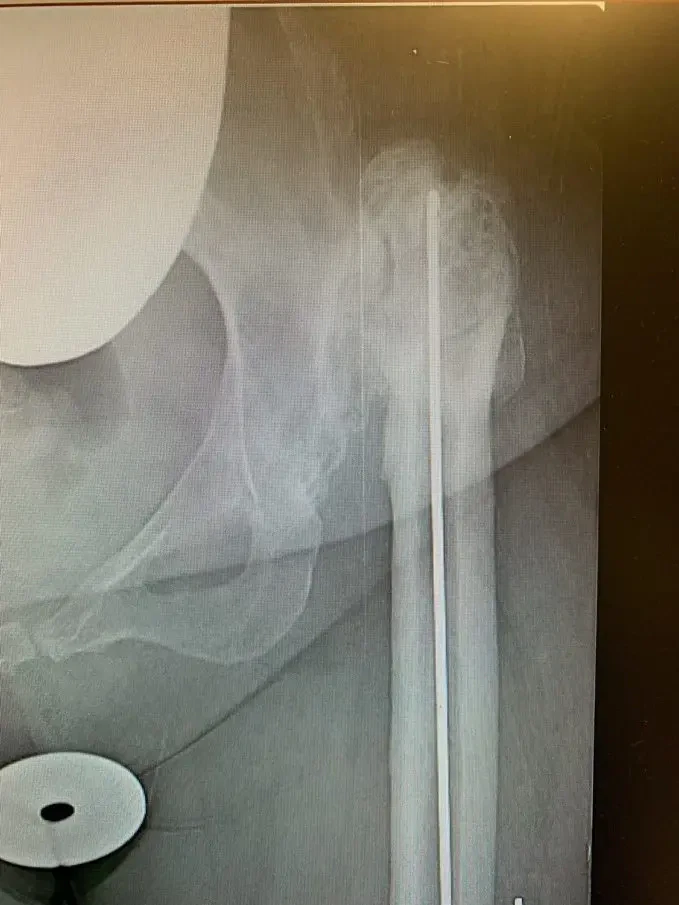

Plain film radiographs revealed a significantly arthritic hip with dysplastic features on both sides of the joint. Her contralateral hip revealed similar findings, but of lesser severity.

A lateral approach to the hip was used, and despite the patients’ abnormal anatomy, exposure of the hip was gained and the broad, shallow acetabulum was identified. The true acetabulum was identified, and the acetabular component was reamed for and placed without event, augmenting fixation with screws.

Accessing the femoral canal proved challenging, the femoral component was prepared. A femoral shortening osteotomy was then performed removing a significant amount of bone to allow for the hip to be relocated without excessive force.

Once this was completed, the definitive femoral component was placed, the osteotomy was fixed and held together with the removed bone acting as autologous bone graft and the hip was relocated.